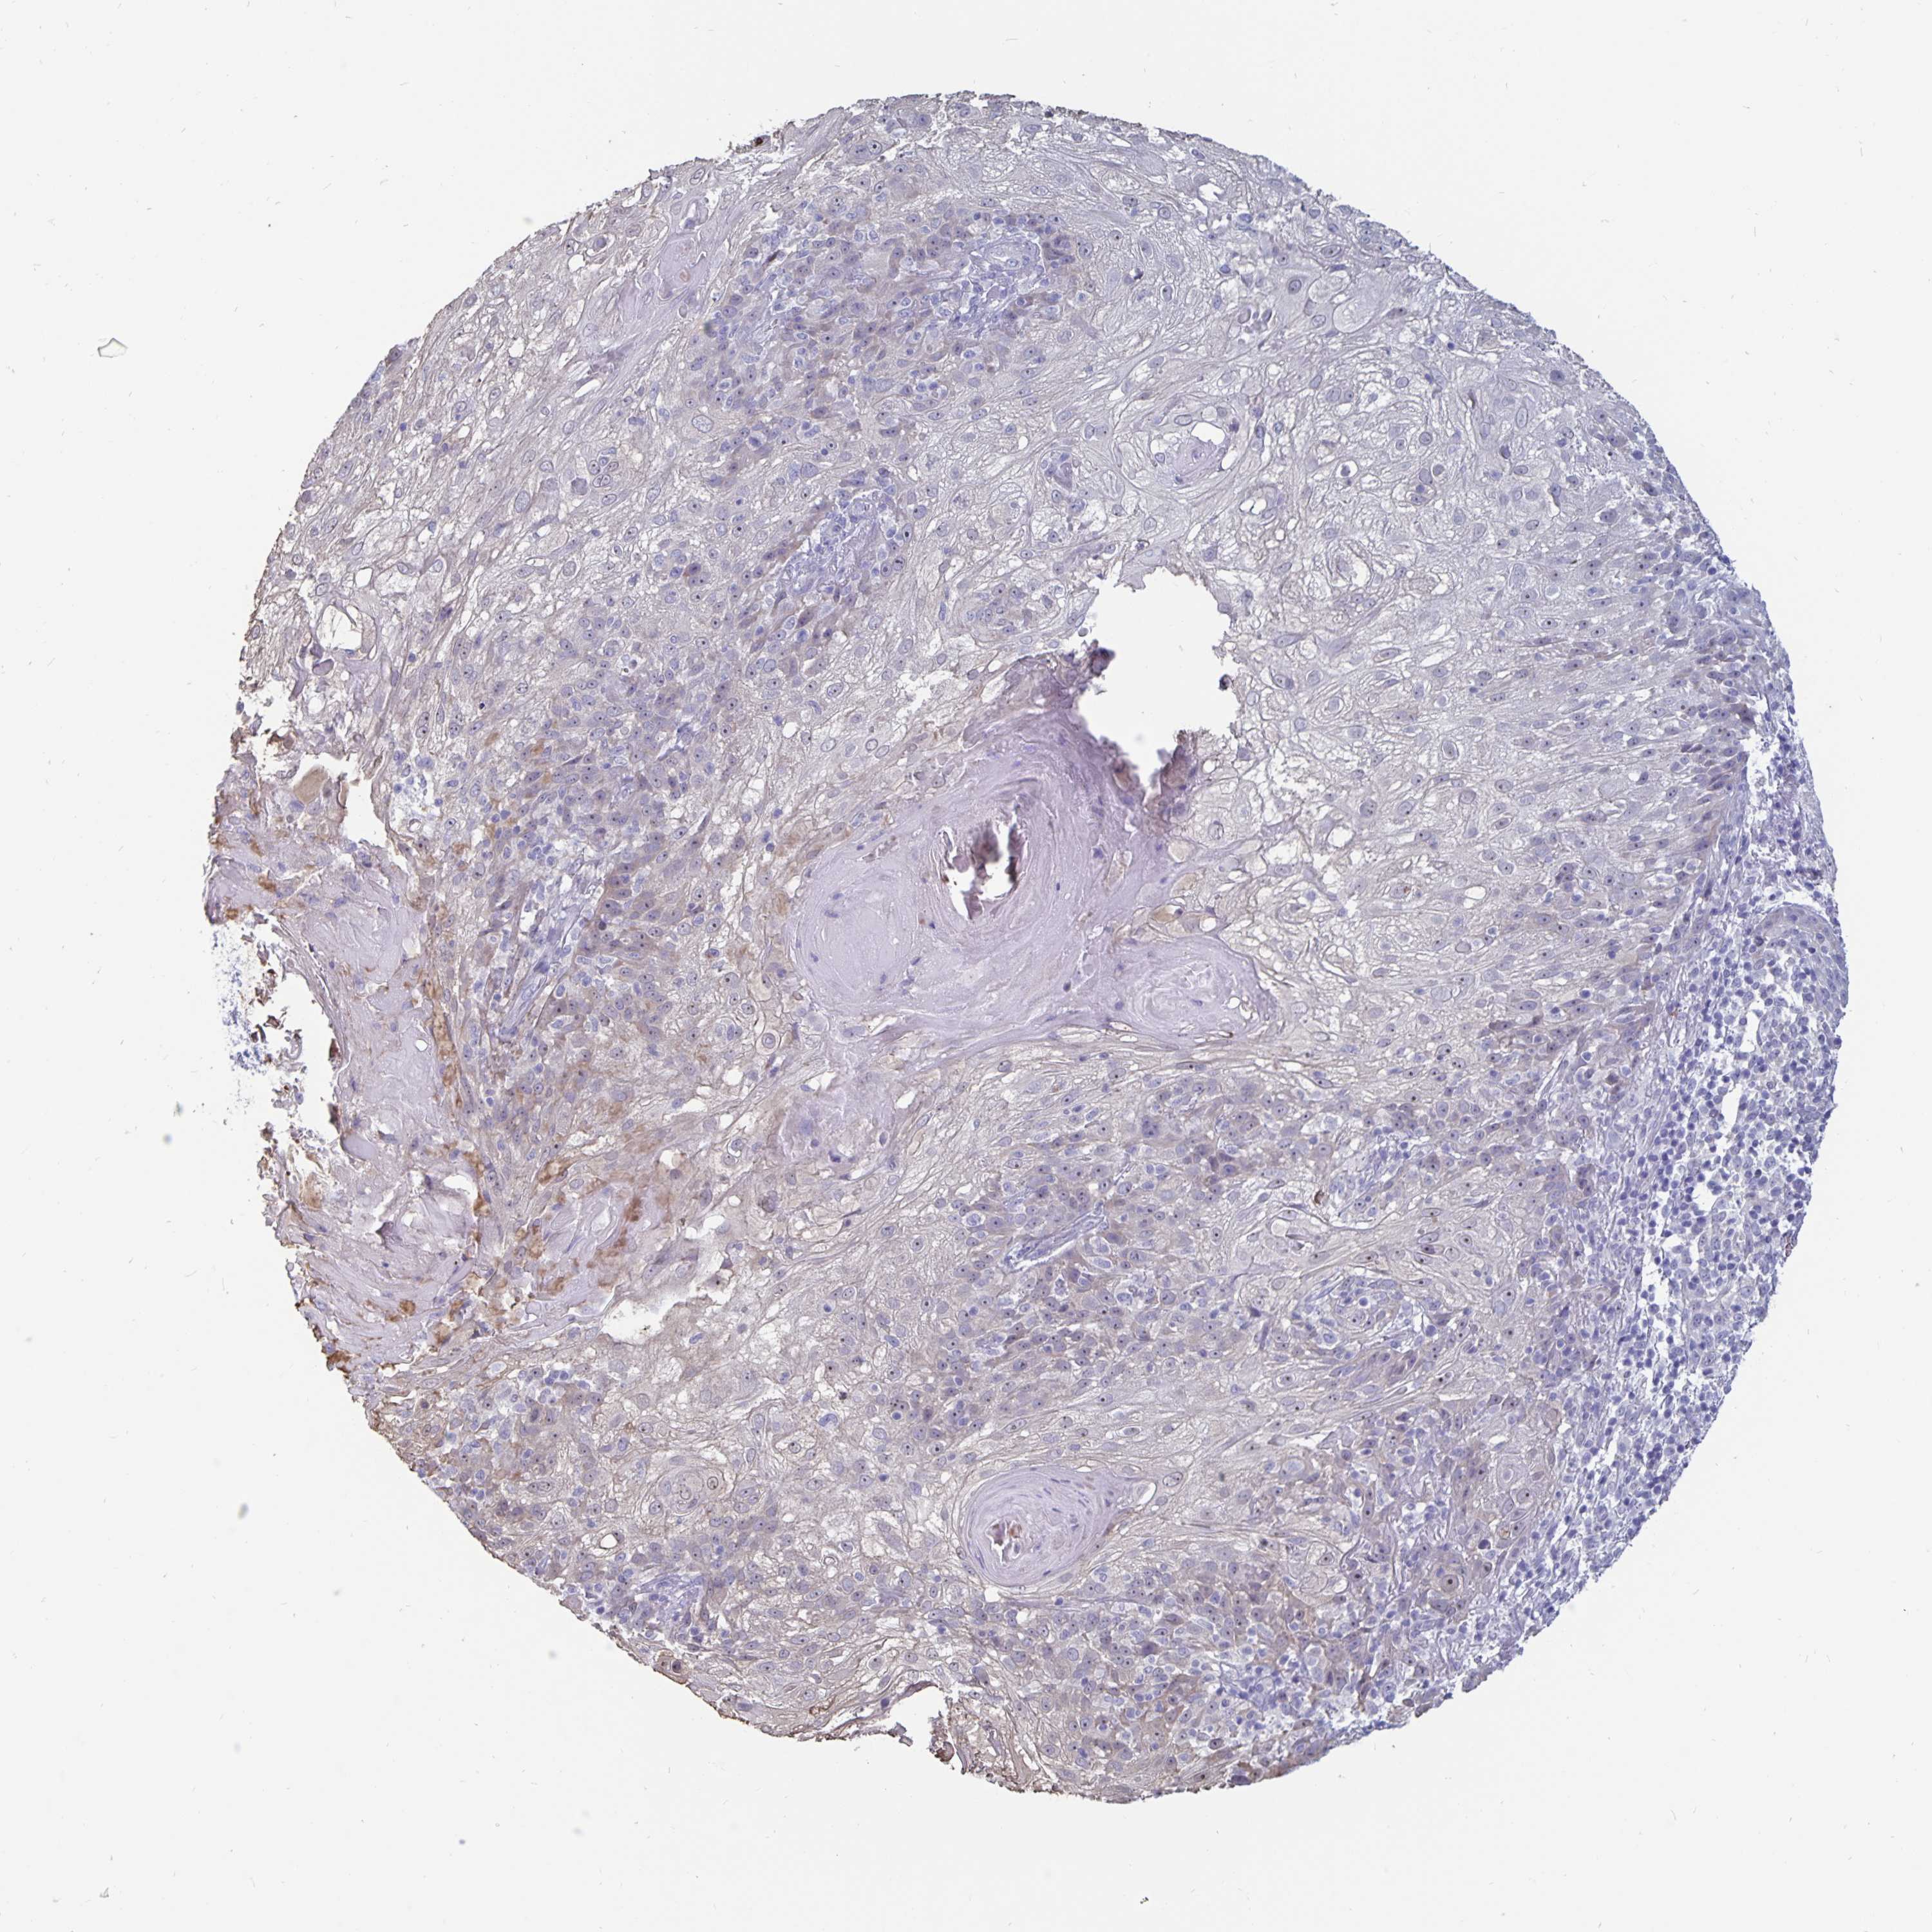

SKIN CANCER - Protein expressioni

A mouse-over function shows sample information and annotation data. Click on an image to view it in a full screen mode. Samples can be filtered based on level of antibody staining by selecting one or several of the following categories: high, medium, low and not detected. The assay and annotation is described here.

Antibody staining in the annotated cell types in the current human tissue is reported as not detected, low, medium, or high, based on conventional immunohistochemistry profiling in selected tissues. This score is based on the combination of the staining intensity and fraction of stained cells.

Each image is clickable and will lead to virtual microscopy that enables deeper exploration of all samples and also displays staining intensity scores, fraction scores and subcellular localization as well as patient and tissue information for each sample.

Antibody CAB009257

Staining

High

Medium

Low

Not detected

Basal cell carcinoma

BCC, high aggressive

Squamous cell carcinoma, NOS